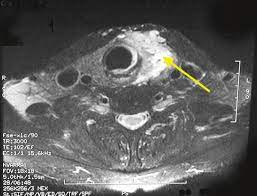

29 years experience ent and head and neck surgery. An ultrasound of the neck is used to examine the carotid arteries located on each side of a patient's neck. Carcinoma of the cervix is a malignancy arising from the cervix. Nearly all skin cancers can be treated effectively if they are found early, so knowing what to look for is important. A neck lump or nodule is the most common symptom of thyroid cancer.

It is the same type of scan that is performed on pregnant women to view images of their unborn babies. Cancerous lymph nodes can occur anywhere on the neck and are typically described as firm, painless, and sometimes may be immovable. This picture gallery contains some examples of the more common. A small device called a transducer is moved over the area. Other names for this test: The arteries deliver blood from your heart to your brain. This gives an idea of how quickly the cancer may develop. Ultrasonography of neck lymph nodes; Epidemiology it typically presents in younger women with an average age of onset at around 45 y. Carotid ultrasound tests for blocked or narrowed carotid arteries, which can increase the. Did the ultrasound show wha. You ob/gyn can usually tell. Carcinoma of the cervix is a malignancy arising from the cervix.

The sonographer stands facing the ultrasound and uses their right hand to move the transducer on the patient's neck, thus simultaneously facing both the ultrasound monitor ( on the left) and the patient's face ( on the right) figure 4.5. Are there signs of thyroid cancer on ultrasound? Sounds like they've been enlarged from an infection, maybe fighting one you weren't even aware of. A neck lump or nodule is the most common symptom of thyroid cancer. How a nodule looks on ultrasound can sometimes suggest if it is likely to be a cancer, but ultrasound can't tell for sure. Physical examination/blood and urine tests. Skin cancer is by far the most common type of cancer. An ultrasound of the neck is used to examine the carotid arteries located on each side of a patient's neck. The doctor will also inspect the nose, mouth, throat, and tongue for abnormalities, often using a light and a mirror for a. During a physical examination, the doctor feels for any lumps on the neck, lips, gums, and cheeks. Unfortunately cancer of the thyroid will not show up on an ultrasound. Most of the time, patients in the low risk group are simply monitored by ultrasound. An ultrasound scanner uses high frequency sound waves to create images of the internal soft tissues of the face and neck.

Doctors often use them to guide a needle during a biopsy. Carotid ultrasound tests for blocked or narrowed carotid arteries, which can increase the. If left unchecked, the cancer can break out of the lymph node and spread to the surrounding. This picture gallery contains some examples of the more common. Ultrasound is relatively quick and simple test that gives very useful information about the soft tissues in the head and neck region including the lymph. Thyroid nodules, or lumps, are very common.most aren't cancer. Reactive lymph nodes look different on ultrasound to lymphoma, so i'm sure the report to the gp will be the same as what she told you. Trusted, accurate neck ultrasound, from the experts in anchorage. The doctor will also inspect the nose, mouth, throat, and tongue for abnormalities, often using a light and a mirror for a. Epidemiology it typically presents in younger women with an average age of onset at around 45 y. Malignant cyst look more complex and may have solid areas. Doctors in 147 specialties are here to answer your questions or offer you advice, prescriptions, and more. Two in three cases of thyroid cancer occur in people under age 55, and 75%.